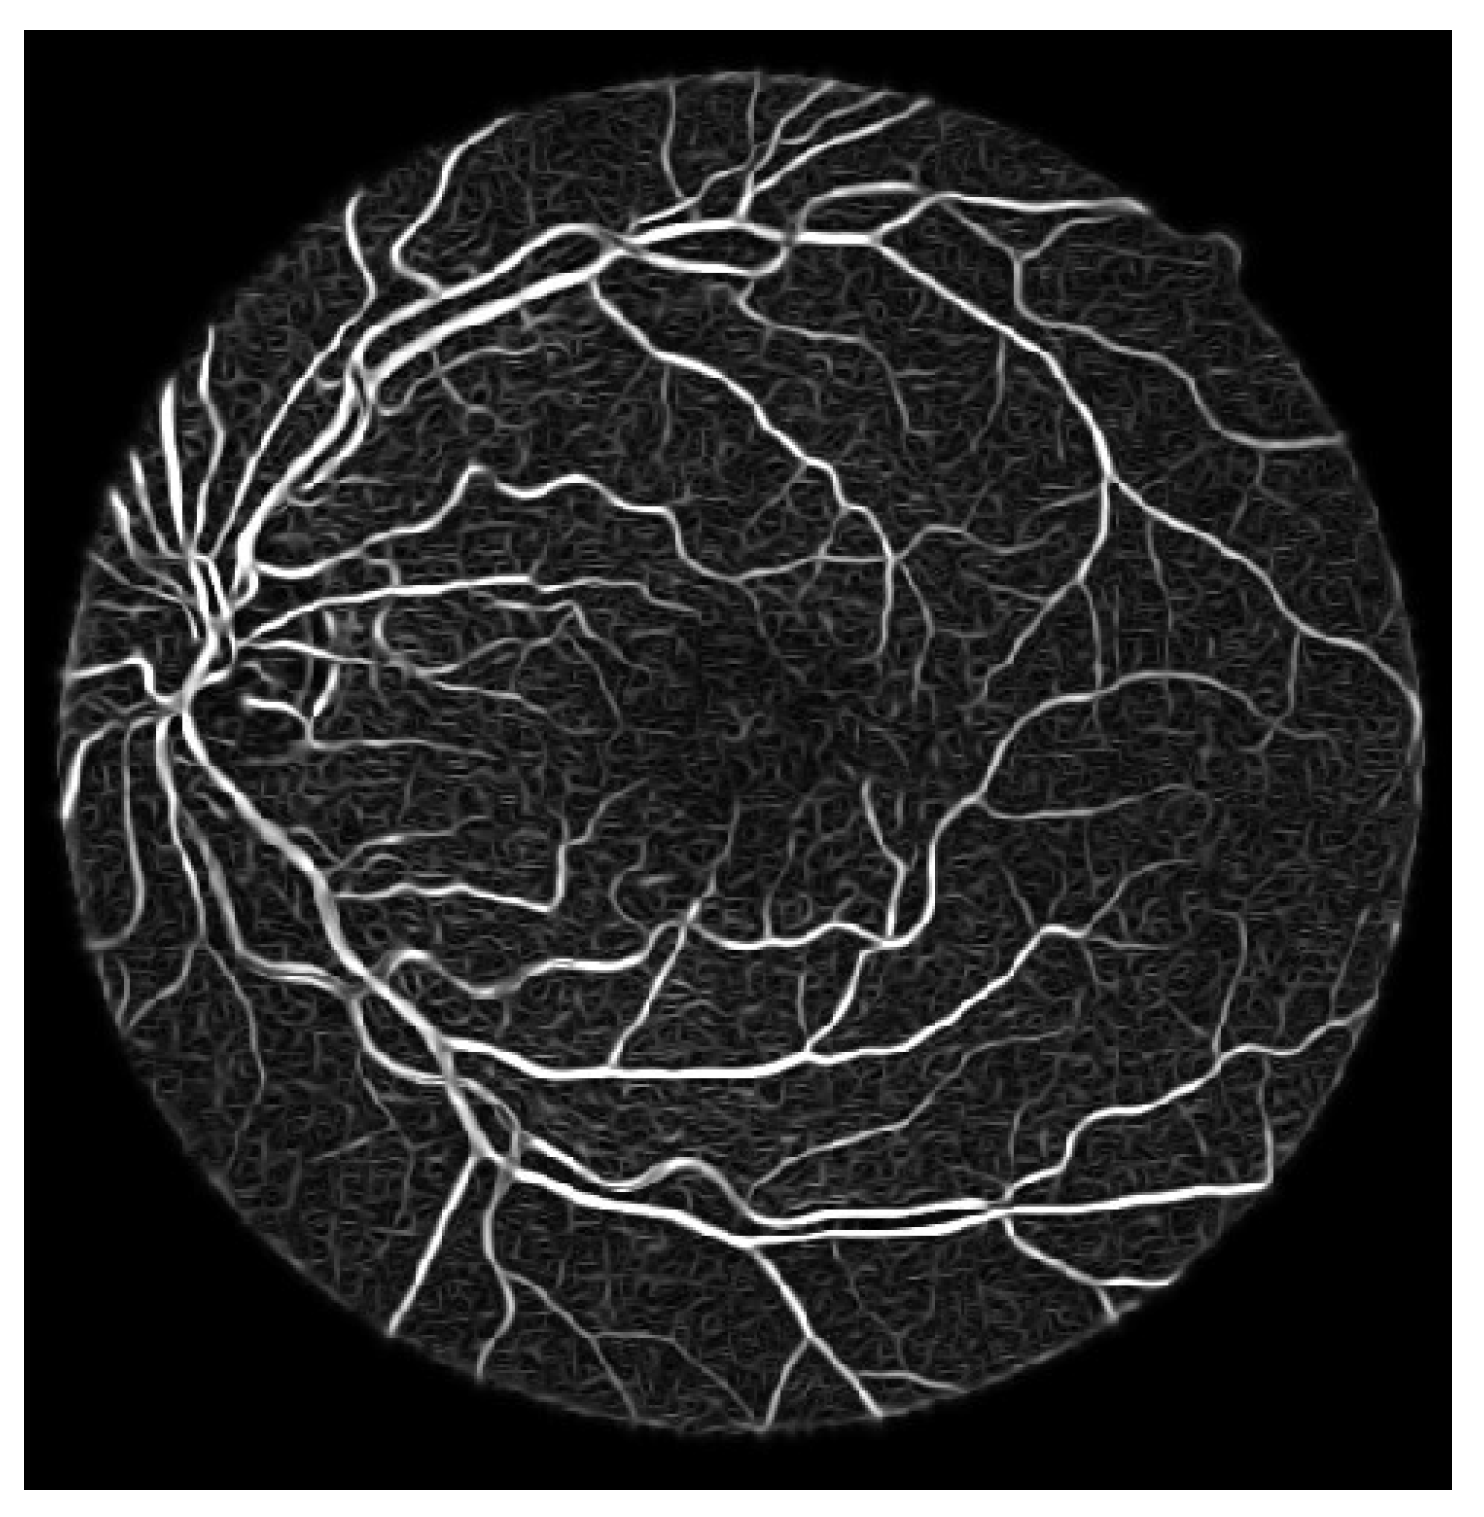

- Process the updated image based on the difference formula depicted equation below and achieved coherent vessels image as shown in Figure 11